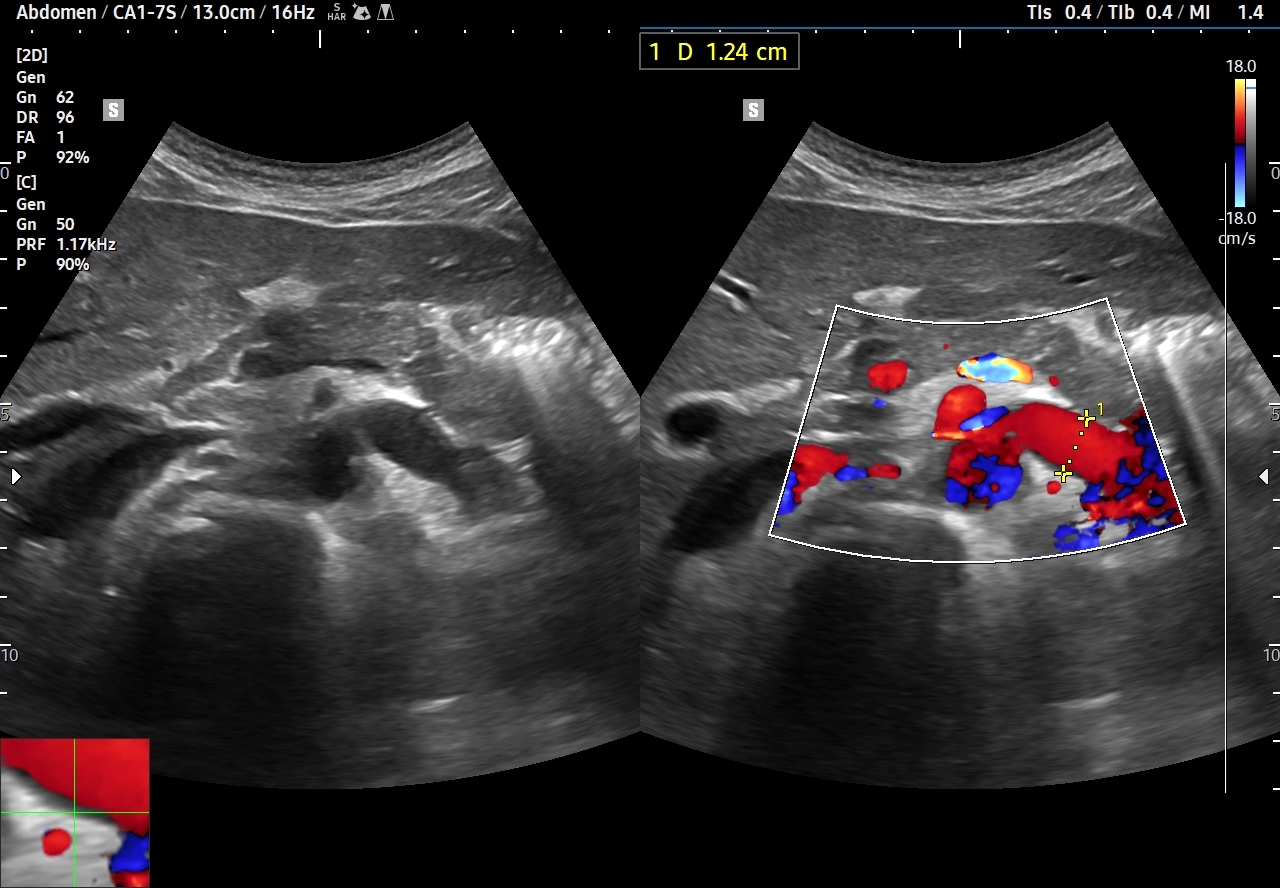

- Ucisk na żyłę nerkową lewą oceniany w trybie B oraz w trybie color-Doppler pod kątem zmniejszenia przekroju żyły i pojawienia się zjawiska aliasingu w zwężeniu. Przy ocenie aliasingu należy aktywnie i rozsądnie operować ustawieniem parametru PRF.

- Zwiększenie prędkości przepływu w miejscu ucisku o 5 lub więcej razy w stosunku do prędkości w nieuciśniętej a poszerzonej żyle nerkowej. Im większy stosunek prędkości tym wiesze prawdopodobieństwo obecności zespołu. W prezentowanym w niniejszym artykule przypadku zarejestrowano ponad 10 krotny wzrost prędkości przepływu.